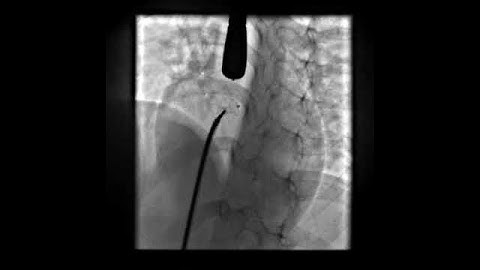

LV Angiogram profiling Perimembranous VSD prior to closure with a symmetrical PMVSDO